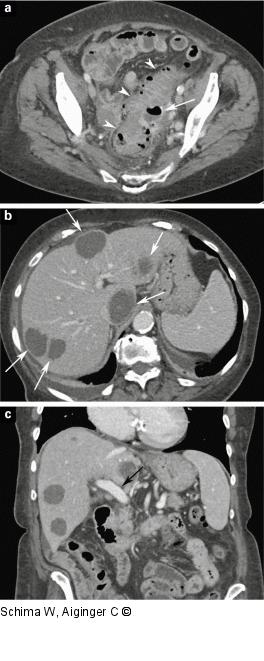

Abbildung 2a-c: MDCT - Leber (a) Die Kontrastmittel-verstärkte MDCT zeigt eine Divertikulitis (Pfeilspitzen) mit einem perikolischen Abszess (Pfeil). (b) Die CT-Schichten durch den Oberbauch zeigen multiple abszessverdächtige zystische Raumforderungen in beiden Leberlappen (Pfeile). (c) In der 3D-Rekonstruktion in koronaler Ebene ist die Pfortader offen (Pfeil), multiple Abszesse sind dargestellt. |

(a) Die Kontrastmittel-verstärkte MDCT zeigt eine Divertikulitis (Pfeilspitzen) mit einem perikolischen Abszess (Pfeil). (b) Die CT-Schichten durch den Oberbauch zeigen multiple abszessverdächtige zystische Raumforderungen in beiden Leberlappen (Pfeile). (c) In der 3D-Rekonstruktion in koronaler Ebene ist die Pfortader offen (Pfeil), multiple Abszesse sind dargestellt. |